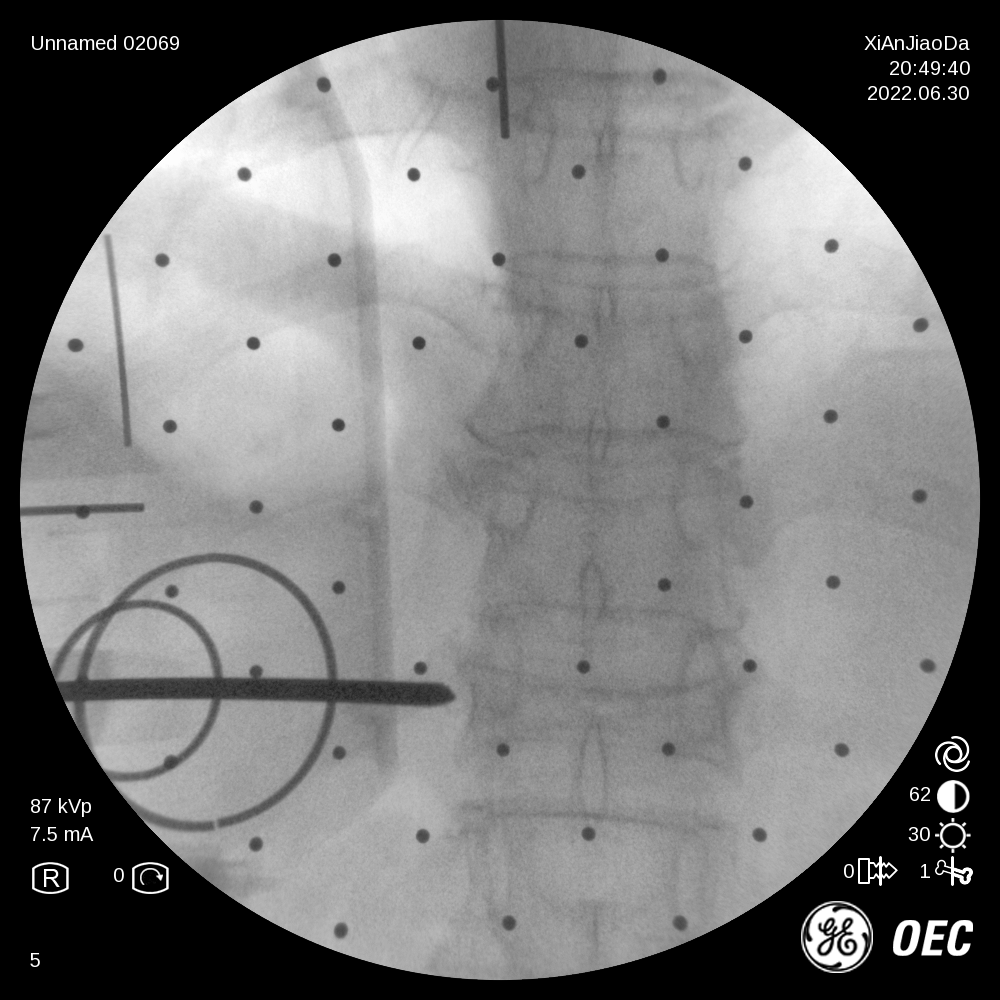

在该机器人辅助手术过程中,仅需通过正侧位进行伤椎识别,通过软件将正侧位透视图与术前规划数据的结合,即可得到病人伤椎的姿态以及实际的穿刺角度,之后机械臂根据软件参数进行精准定位,手术医生在机械臂引导下一次性进针成功,并对进针位置角度表示满意,整个过程少于20分钟,实现了手术的更精准化、高效化。相较于传统定位流程,术前规划只能保存在医生脑海中,术前与术中流程无法很好的衔接,术中穿刺依赖医生丰富的经验,对于情况复杂的病人,术中需要反复试验,导致手术时间延长、患者受辐射量增加。后续放置球囊、注入骨水泥等操作则同传统手工操作。